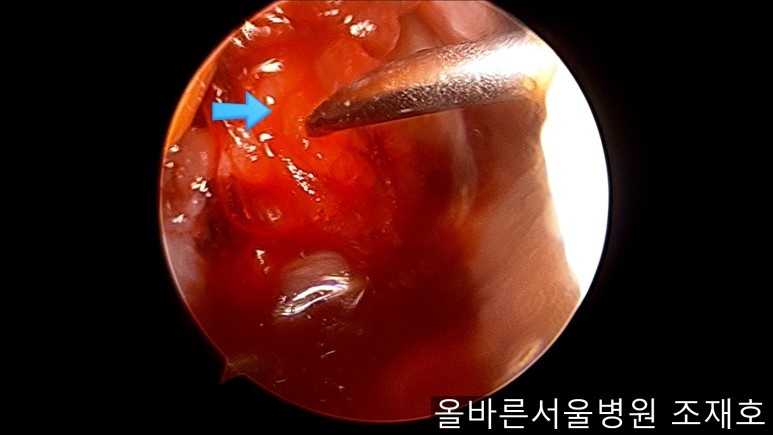

为了软骨再生,在胫骨上端进行微骨折术。

胫骨上端是通过微骨折术,可再生软骨的地方。

尽量将孔打地细密,确认此处骨髓腔内的血流出。